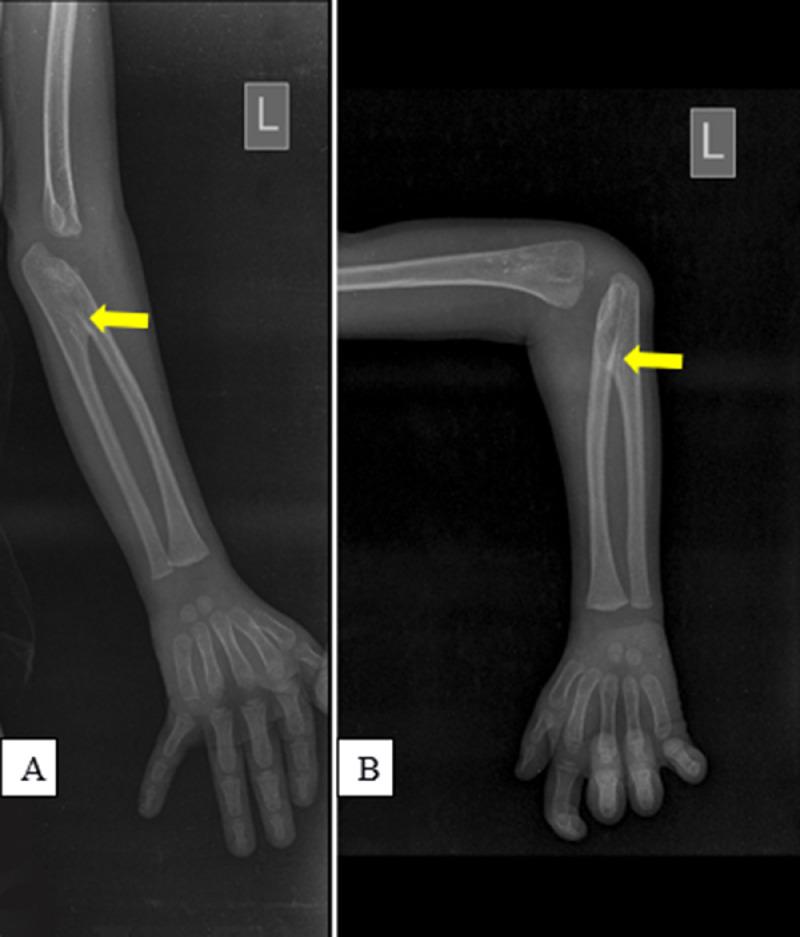

Unilateral congenital proximal radioulnar synostosis in a 4-year-old boy: A case report.

Congenital radioulnar synostosis is a rare musculoskeletal disorder of the elbow, occurring as a result of variable degree and length of the congenital fusion of the proximal radioulnar joint. Patients presents early to the hospital depending on the severity of the synostosis and its effect on elbow function. It may have psychosocial effects on the affected individuals as they grow older especially when the deformity is dramatic. Treatment may be conservative, surgical (which may have a variable degree of success) and psychotherapy.